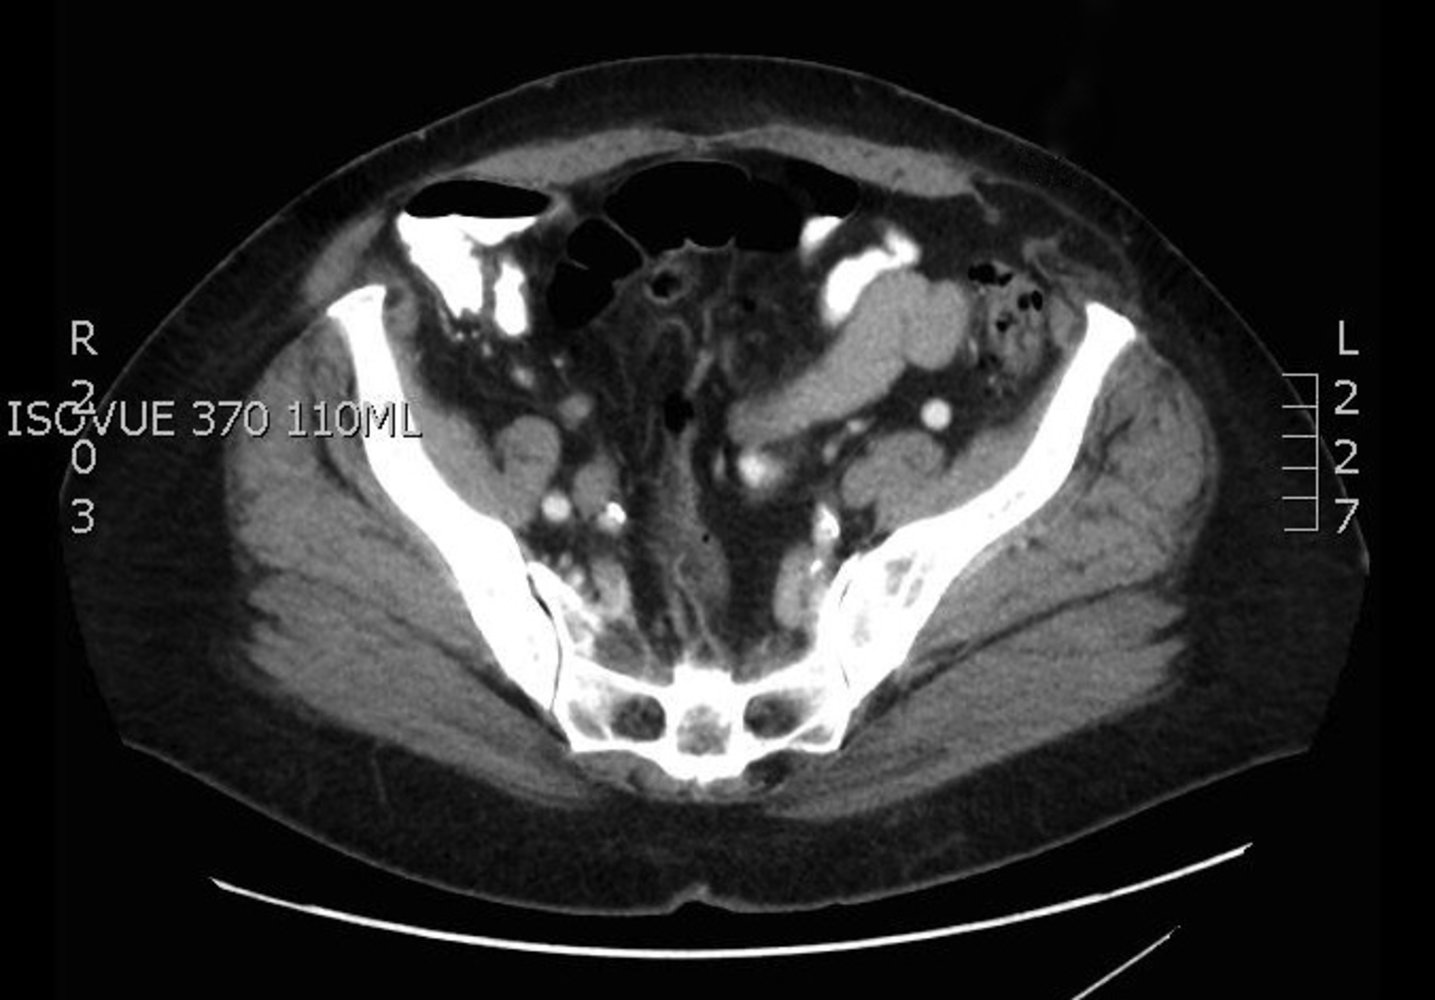

• CT abdomen

• Sensitive imaging study for suspected bowel obstruction or strangulation [10]

• Typically performed with both IV and PO contrast (unless contraindicated because of obstruction)

• Can facilitate planning for complex hernia repair [23]

Findings

• Direct visualization and quantification of the fascial defect(s)

• Presence of viscera in the hernial sac

• Strangulated hernia: signs of visceral ischemia [25]

• Obstructed hernia: radiological signs of mechanical bowel obstruction